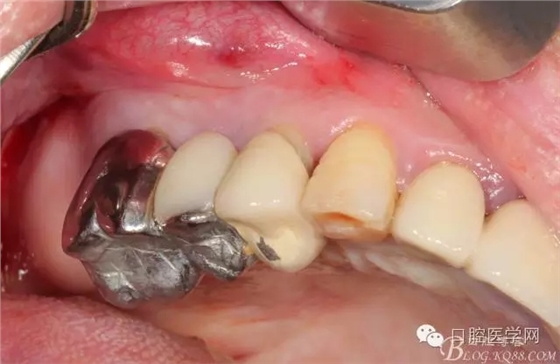

拔掉以后(這樣能夠整體拔出 說明這組牙是非常松動(dòng)了)

拔牙以后 拔牙窩少許肉芽 發(fā)現(xiàn)13遠(yuǎn)中還是有些肉芽的

簡(jiǎn)單清理以后 (一般這種情況我是不太翻瓣的)這個(gè)患者我在清理13遠(yuǎn)中時(shí)候我發(fā)現(xiàn)有些肉芽而且超過了我的預(yù)期的量,我開始不太淡定了 。 我在想牙周科同事是不是知道我要拔牙,沒有在14 16 牙位用洪荒之力刮治啊。結(jié)果我翻瓣一點(diǎn)點(diǎn)去檢驗(yàn)了下牙周科刮治的效果,那么結(jié)果是非常好,沒啥太多的肉芽,不翻瓣完全可以刮干凈,看來我得信任我的同事啊,牙周科非常給力。13牙位遠(yuǎn)中的肉芽估計(jì)的確不好刮掉,所以留給我刮了吧。